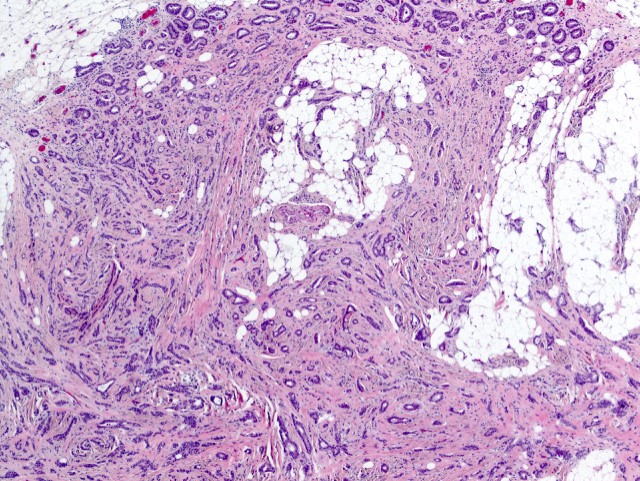

Microscopic (histologic) description

- Histologic grading is based on the Nottingham / modified Bloom & Richardson Score (Histopathology 1991;19:403):

- Histological features of IBC NST vary considerably from case to case and even within the same case

- Margins vary from highly infiltrative, permeating the surrounding tissue, to continuous pushing margins

- Architecture varies from sheets, nests, clusters, cords or individual cells (but lacks the cytomorphological characteristics of invasive lobular carcinoma)

- Tubular formations are prominent in well differentiated tumors but absent in poorly differentiated tumors

- Calcification in 60% of cases, variable necrosis

- Often ductal carcinoma in situ (DCIS) (up to 80%)

- In some cases, DCIS is extensive

- Associated DCIS is usually of same nuclear grade as the invasive carcinoma

Microscopic (histologic) images

Contributed by Julie M. Jorns, M.D., Kristen E. Muller, D.O., Gary Tozbikian, M.D. and Emad Rakha, M.D.